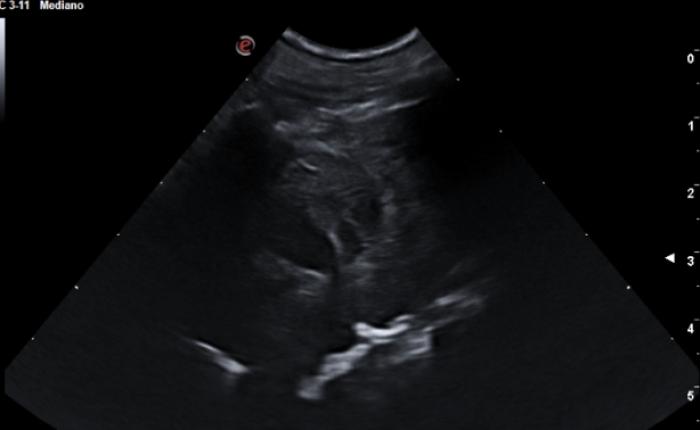

Signo de cortina

Se trata de la transición vertical que podemos evaluar entre el pulmón aireado y las estructuras abdominales tras el diafragma (hígado, estómago, etc.), este último no será visible dada la curvatura que presenta. En condiciones normales observaremos como la expansión pulmonar durante la inspiración hace que el área aireada se extiende caudalmente ocupando los penúltimos espacios intercostales, para seguidamente dirigirse cranealmente dando el efecto de “descorrer una cortina”. Este signo se perderá ante la presencia de consolidación caudal del pulmón o en presencia de derrame pleural (Vídeo 2).